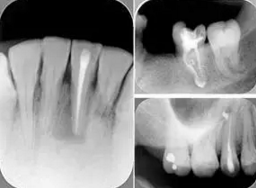

6. 術(shù)后 X 線片

術(shù)后 X 線片用來評定根管充填 長度、致密度(管壁清晰、側(cè)枝)等指標(biāo)。

圖為根管充填術(shù)后 X 線片。圖中可見,根管充填較好。右下圖有白色小點(diǎn),為側(cè)方加壓導(dǎo)致糊劑擠出所致,表明根管充填比較致密。

致密、恰到好處的充填可去除干凈根管里感染灶,機(jī)體逐漸恢復(fù)。

多根牙時候需進(jìn)行偏移投照,正位投照無法說明具體哪根牙根管充填效果。